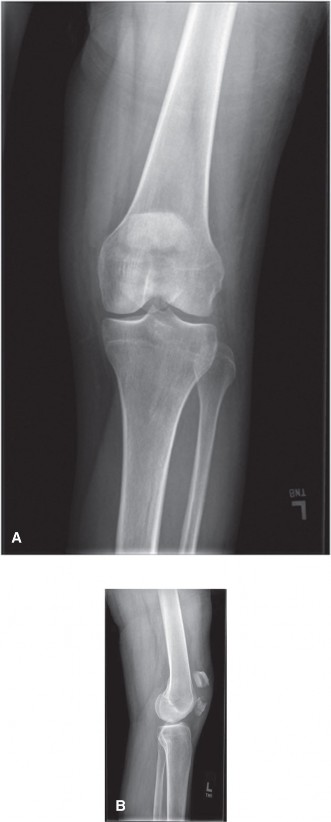

A 48-year-old woman presents to the emergency department complaining of acute left knee pain and inability to…

A 48-year-old female patient presents with anterior left knee pain. She has had a history of recurrent patell…